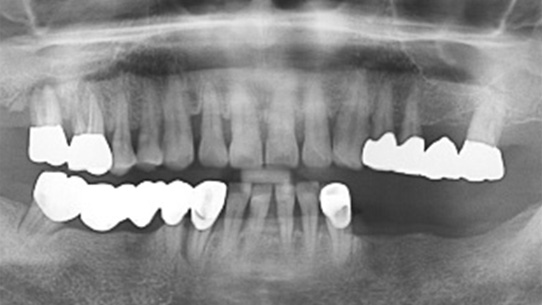

30대 남환으로 다른 치과에서 임플란트 5개 진단을 받고 내원. 빈 공간을 활용하여 돌출입 교정치료를 하고 임플란트를 최소로 하는 것을

목표로 교정 계획을 세움. 잔존하는 치아뿌리를 모두 제거하고 전치의 전방 견인하는 교정치료를 진행하였습니다.

치아가 상실된 부위 공간을 사랑니를 활용하여 모두 매꿔 임플란트 개수를 5개에서 1개로 감소. 또한 상실된 부위의 잇몸 뼈 높이가 높아져 예전보다

건강해 졌으며, 입술 외모가 개선되었습니다.